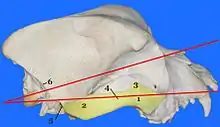

The cephalic index or cranial index is a number obtained by taking the maximum width (biparietal diameter or BPD, side to side) of the head of an organism, multiplying it by 100 and then dividing it by their maximum length (occipitofrontal diameter or OFD, front to back). The index was once used to categorize human beings in the first half of the 20th century, but today it is used to categorize dogs and cats.

Technically, the measured factors are defined as the maximum width of the bones that surround the head above the supramastoid crest (behind the cheekbones), and the maximum length from the most easily noticed part of the glabella (between the eyebrows) to the most easily noticed point on the back part of the head.

Medicine

The cephalic index is also used in medicine, especially in the planning and effectiveness analysis of cranial deformity corrections.[10] The index is a useful tool in assessing the morphology of cranial deformities in clinical settings.[11] The index is used while looking at the fetal head shape, and can change in certain situations (ex. breech presentation, ruptured membranes, twin pregnancy).[12]